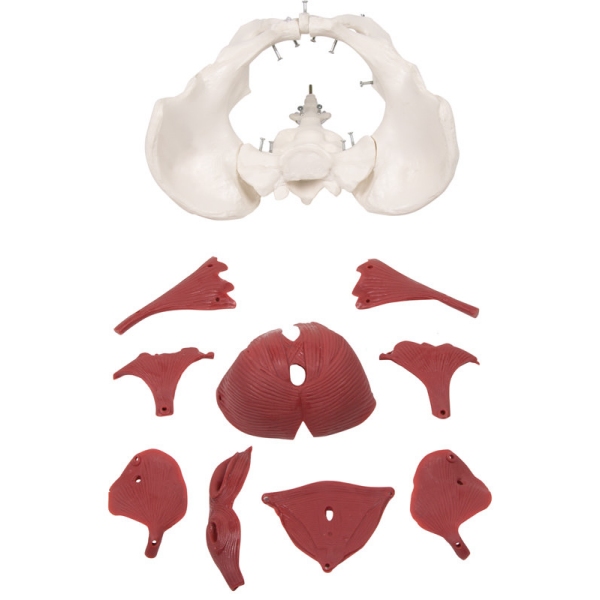

Model ženskega medeničnega dna, 12 delov

Ta novi model ženske medenice z muskulaturo medeničnega dna predstavlja medenično dno v svojih plasteh. Predstavljene so naslednje mišice, ki jih je mogoče odstraniti:

- Obturatorius internus mišica (levo in desno)

- Piriformis mišica (levo in desno)

- Coccygeus mišica ( levo in desno)

- Medenična diafragma (mišica levator ani, sestavljena iz mišice puborectalis, mišice pubococcygeus in mišice iliococcygeus)

- Urogenitalna diafragma (sestavljena iz globoke prečne mišice presredka, površinske prečne mišice presredka in mišice ischiocavernosus)

- Sfinkterji urogenitalni in prebavni trakt (sestavljen iz zunanjega analnega sfinktra, sečnice in mišice bulbospongiozne)

Skupaj z dvema kolčnima kostema in križnico je model sestavljen iz skupno 12 delov. Mišice so pritrjene z zatiči, kar omogoča njihovo odstranitev za prikaz plasti. Ta model je popoln za tečaje gimnastike medeničnega dna, za tečaje priprave na porod, za izobraževanje babic ali preprosto za anatomske študije medeničnega dna.

Velikost: 27 x 18 x 17 cm

Teža: 1 kg